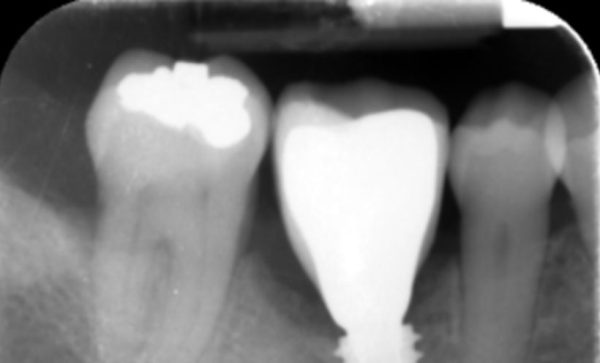

Case 12